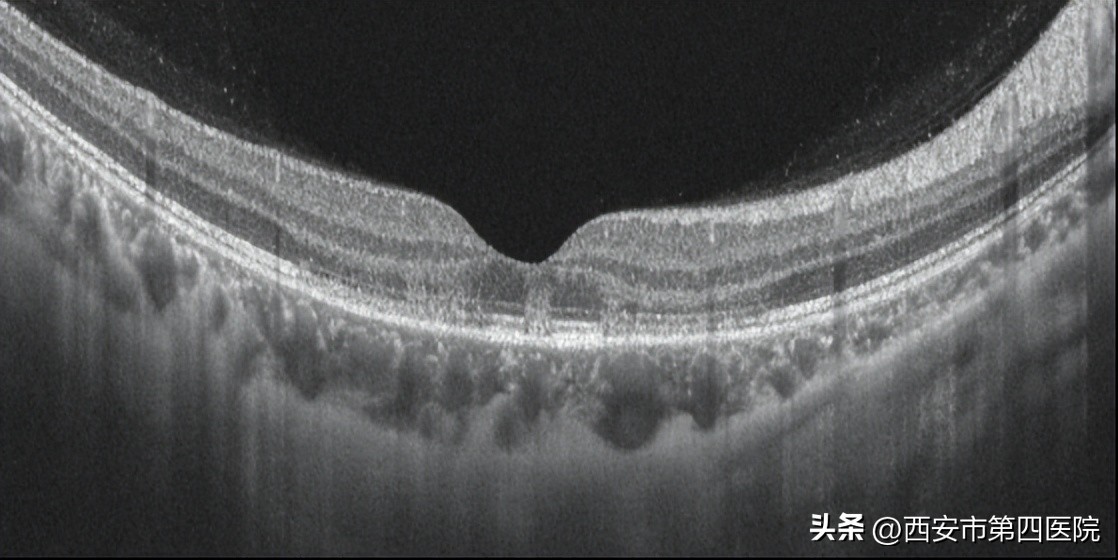

双眼眼底OCT检查: 外核层、外丛状层强反射灶,椭圆体带、嵌合体带结构不连续。

OCT检查提示:双眼外核层、外丛状层强反射灶,椭圆体带、嵌合体带结构紊乱,甚至断裂。